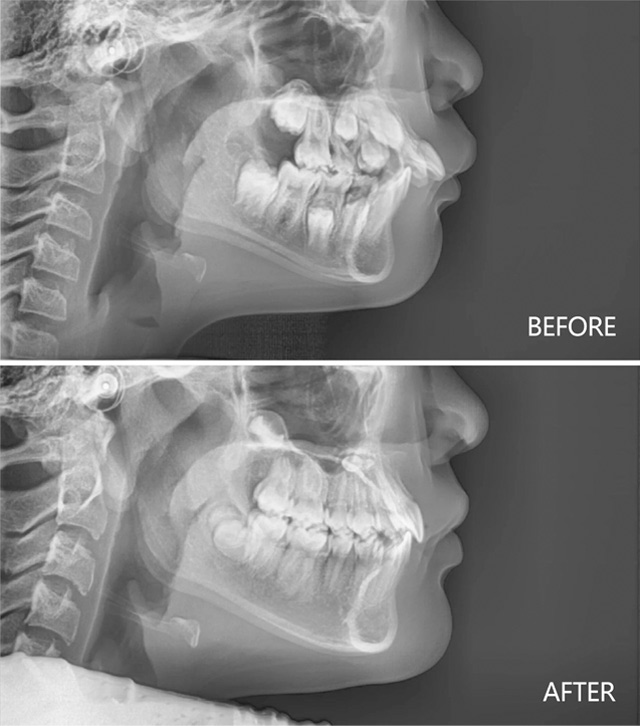

下巴后缩合并深覆盖治疗前后